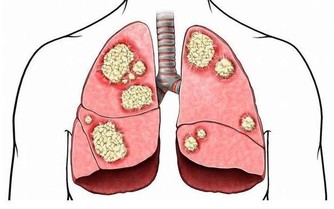

三、維生素C

維生素C抗氧化效果明顯,有利於促進人體新陳代謝速度,抑制黑色素形成,幫助皮膚變得白皙。維生素C在治療敗血症方面還有重要作用。

如果人體缺乏維生素C,就會對健康帶來嚴重影響,包括敗血症、牙周出血、蛀牙、多汗、軟骨病等。

所以,平時也要注意攝取維生素C,即可以服用一些藥片,也可以多吃檸檬、獼猴桃、西紅柿等果蔬。